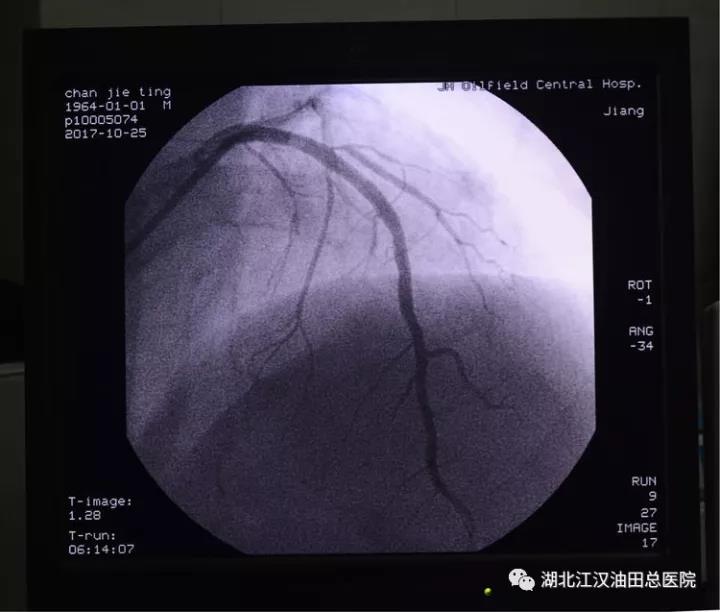

5:56分,心脏血管造影结束,诊断为左前降支血管闭塞。马上开通闭塞血管,植入支架。

6:10分,支架安装完毕,闭塞的血管血流恢复,心肌将重新得到灌注。